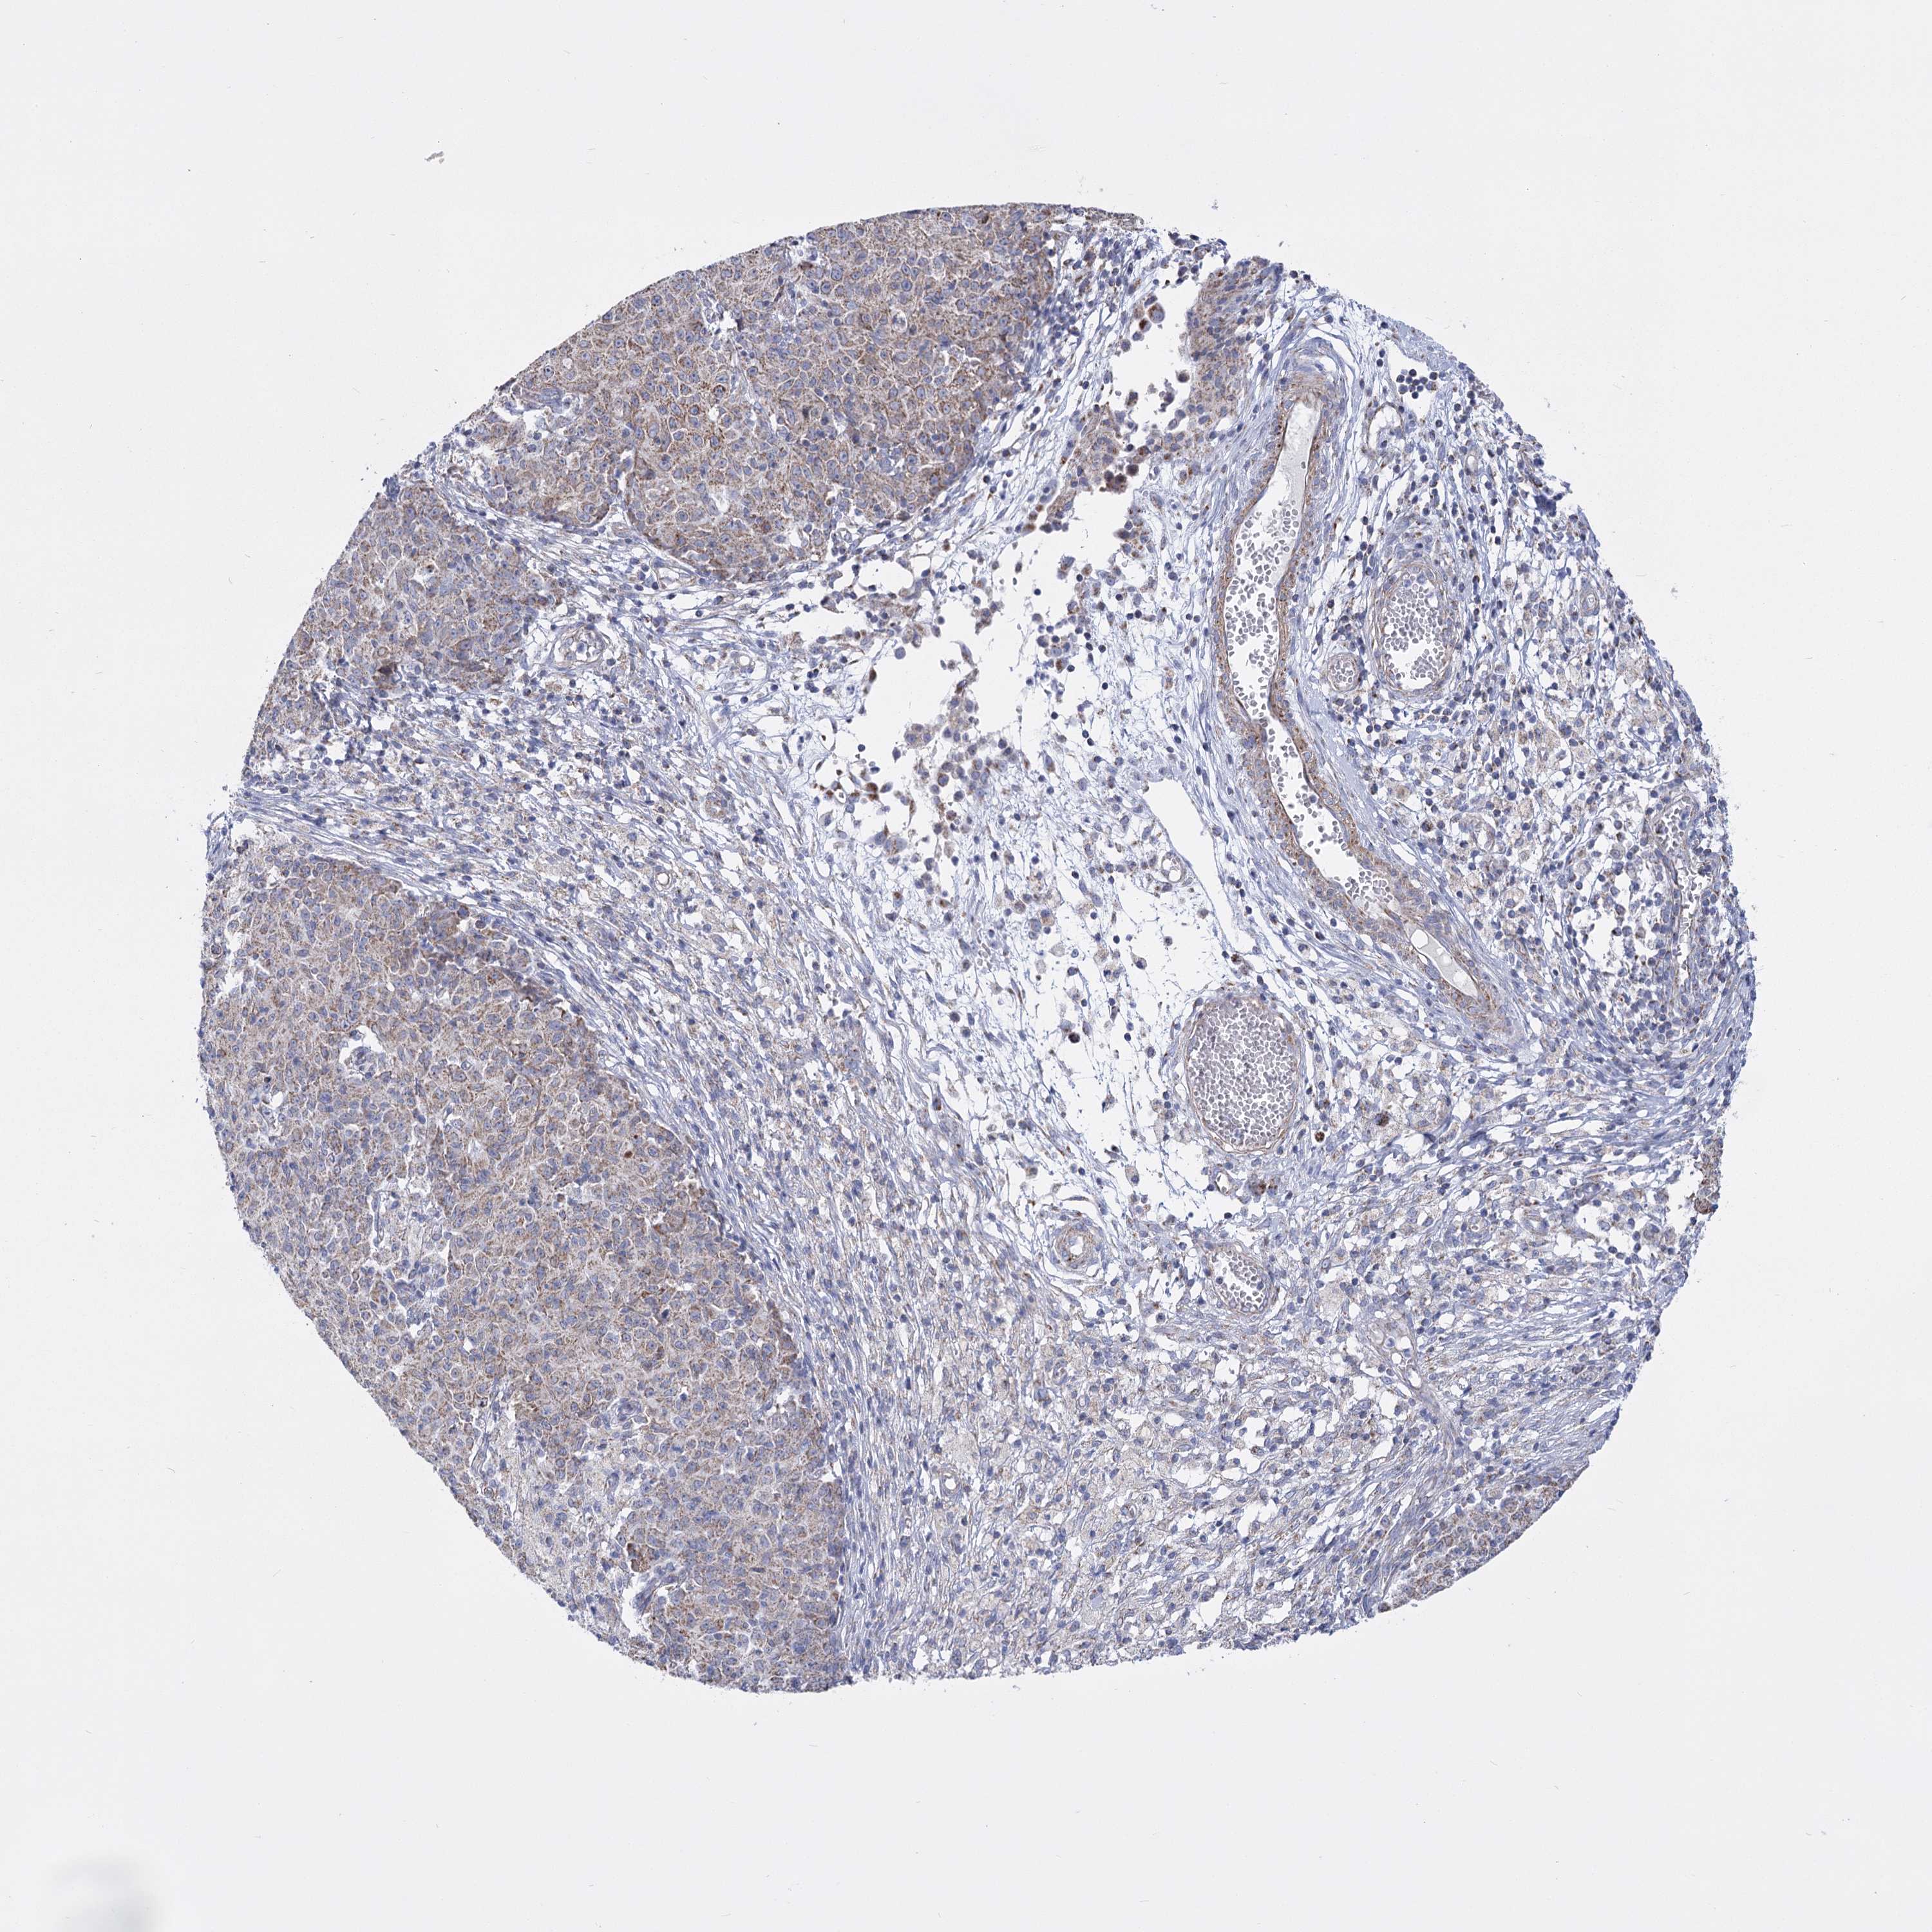

OVARIAN CANCER - Protein expressioni

A mouse-over function shows sample information and annotation data. Click on an image to view it in a full screen mode. Samples can be filtered based on level of antibody staining by selecting one or several of the following categories: high, medium, low and not detected. The assay and annotation is described here.

Note that samples used for immunohistochemistry by the Human Protein Atlas do not correspond to samples in the TCGA dataset.

Antibody stainingi

Antibody staining in the annotated cell types in the current human tissue is reported as not detected, low, medium, or high, based on conventional immunohistochemistry profiling in selected tissues. This score is based on the combination of the staining intensity and fraction of stained cells.

Each image is clickable and will lead to virtual microscopy that enables deeper exploration of all samples and also displays staining intensity scores, fraction scores and subcellular localization as well as patient and tissue information for each sample.

Antibody HPA036744

Antibody HPA036745

Antibody CAB033794

Staining

High

Medium

Low

Not detected

Cystadenocarcinoma, serous, NOS